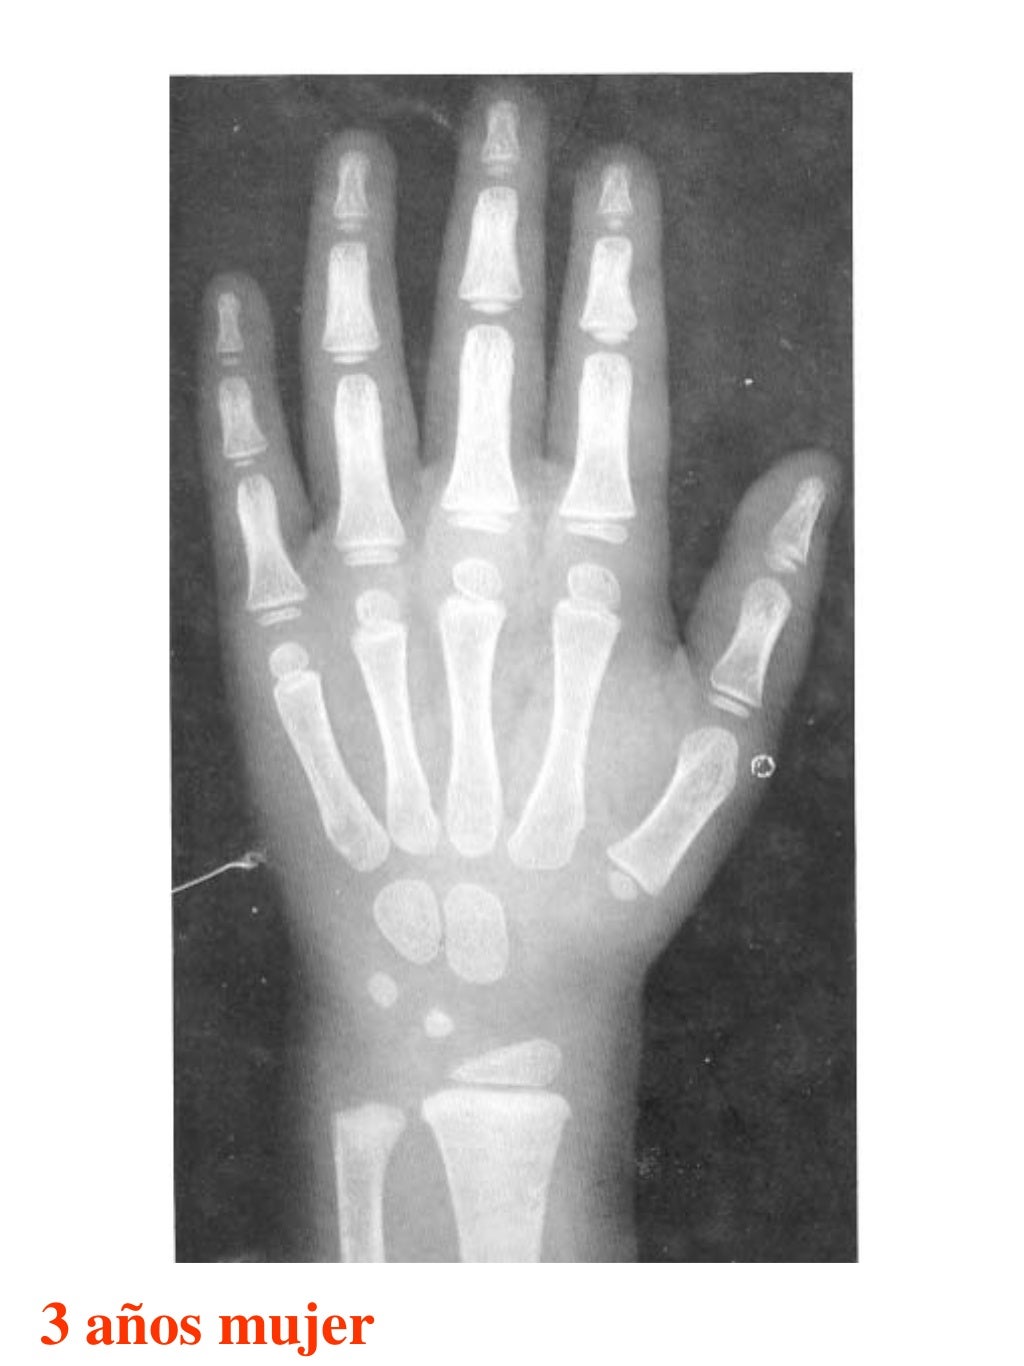

Tablas De Greulich Y Pyle The standards established by greulich and pyle, undoubtedly the most popular method, consist of two series of standard plates. The standards established by greulich and pyle, undoubtedly the most popular method, consist of two series of standard plates. El documento lista las edades. This systematic review summarizes the. The greulich and pyle method is one of the two main ways to assess the bone age of children. Both main methods of bone age. Scribd is the world's largest social reading and publishing site. 153 recomendaciones • 616,869 vistas. Atlas greulich y pyle | pdf | descarga gratuita. The greulich and pyle atlas is used to estimate the age of children and adolescents. The radiographic atlas of skeletal development of the hand and wrist by ww greulich and si pyle is a classic radiological.

Atlas greulich y pyle Tablas De Greulich Y Pyle The standards established by greulich and pyle, undoubtedly the most popular method, consist of two series of standard plates. Atlas greulich y pyle | pdf | descarga gratuita. Scribd is the world's largest social reading and publishing site. 153 recomendaciones • 616,869 vistas. The radiographic atlas of skeletal development of the hand and wrist by ww greulich and si pyle. Tablas De Greulich Y Pyle.